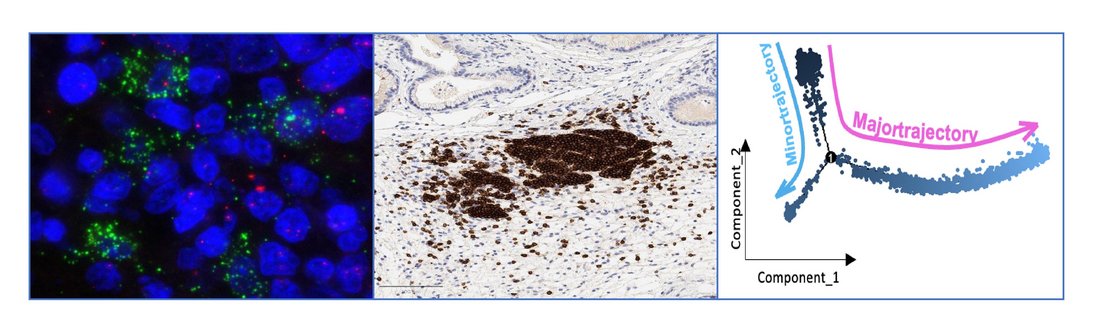

We investigate the multifaceted roles of B lymphocytes within solid tumour microenvironments, focusing on how they infiltrate tumour tissue, undergo phenotypic adaptation, and organise into structures such as tertiary lymphoid structures (TLSs). Our research explores the dynamic interactions between B cells and other immune or stromal components, including T cells, macrophages, and cancer-associated fibroblasts, and how these cellular dialogues can either promote anti-tumour immunity or support immune evasion and tumour progression.

Using advanced immunophenotyping (including flow cytometry, multiplex immunofluorescence, bioinformatic analysis, and functional co-culture models), we aim to define the determinants of B-cell fate and function in the tumour context. Ultimately, our goal is to uncover novel principles of B-cell-mediated immune regulation in cancer and to leverage this knowledge to develop innovative immunotherapeutic strategies that improve patient outcomes.